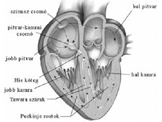

• Az agy vérellátása, vizsgálata, kezelése